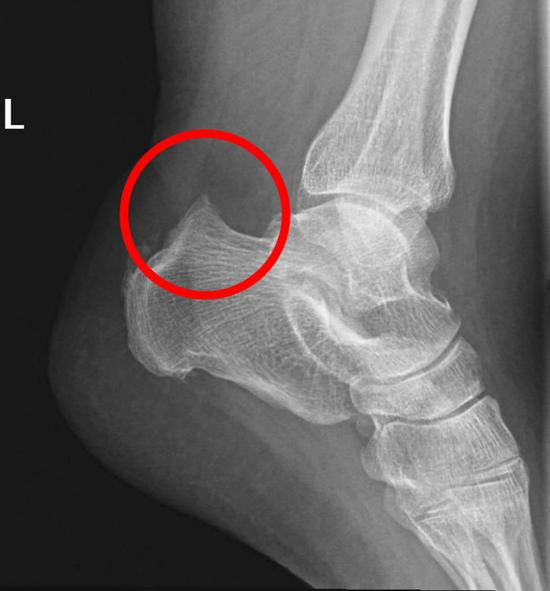

鲁普是在去年芝加哥马拉松赛后接受手术的,原因是他被一种名为 Haglund畸形 的跟骨疾病困扰。

Haglund畸形往往表现足跟骨的背面骨质凸起。

这个凸起恰恰可能与跟腱附着处产生应力集中现象以及摩擦,从而导致疼痛,这个疾病最早由帕特里克・哈格伦德(PatrickHaglund)医生于1927年发现,因此被命名为Haglund畸形。

如果保守治疗不能有效缓解疼痛,医生可能会建议手术切除骨嵴或修复跟腱。

Haglund畸形往往发生于先天遗传,这样的人群如果正常生活也许并不发生症状,但如果是运动员,需要反复牵拉跟腱,就容易导致畸形突出处与跟腱发生摩擦,严重时,甚至可以导致跟腱断裂。

Haglund畸形常常表现为跟骨结节后外侧的突出,往往合并跟腱滑囊炎。

这也导致Haglund畸形往往被诊断为跟腱滑囊炎,主要表现为脚跟处疼痛、局部肿胀。

跟腱两侧可见膨出,局部皮肤温度可升高,跟腱内外侧均可有压痛,被动背伸踝关节可加重疼痛。只有经过影像学检查,才能明确跟骨是否存在发育异常,

如果疼痛部位不是在腱体上,而是在跟腱连接跟骨的位置(也就是说疼痛部位更低),那么除了跟腱病,也有可能是足跟滑囊炎、跟骨Haglund畸形等等;